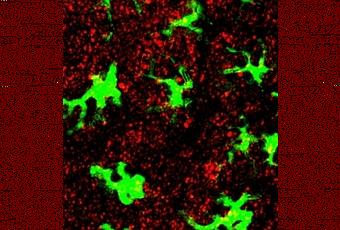

Celulas inmunes, señaladas con una proteina verde fluorescente, rodeadas por nanoparticulas (rojas), depues de que estas hayan sido inyectadas bajo la piel de un raton. Fuente: MIT.